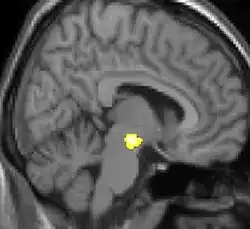

| Voxel-based morphometry shows brain area structural differences. | ||

Positron emission tomography (PET) scans indicate the brain areas which are activated during attack only, compared to pain free periods. These pictures show brain areas that are active during pain in yellow/orange color (called "pain matrix"). The area in the center (in all three views) is activated only during cluster headaches. The bottom row voxel-based morphometry shows structural brain differences between individuals with and without CH; only a portion of the hypothalamus is different.[36]